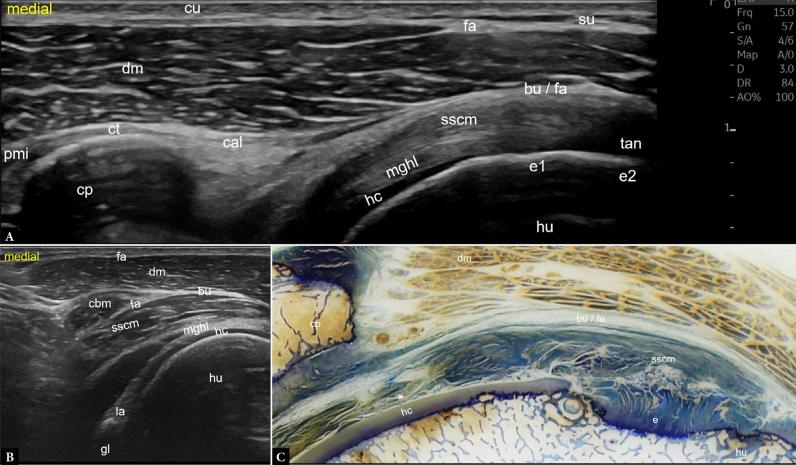

推进高分辨率肌肉骨骼超声:一种基于组织学和解剖学的方法以增强肩部成像。第2部分:肩部前侧和外侧

Advancing high-resolution musculoskeletal ultrasound: a histology- and anatomy-driven approach for enhanced shoulder imaging. Part 2: Anterior and lateral shoulder.

Ultrasonography is a reliable imaging technique for the accurate diagnosis and evaluation of musculoskeletal disorders. Recent developments in ultrasound technology have significantly increased image resolution, making it possible to see anatomical features at almost microscopic dimensions. Current standards for standardized shoulder ultrasonography mostly depend on outdated machine types and configurations that may not fully utilize these high-resolution imaging capabilities. In this article, we give a clear and comprehensive introduction to high-resolution shoulder sonography, using histological and anatomical images from cadavers for comparison. Images collected using contemporary technology are shown, and international standard practices are considered. The examination and normal results are presented in a methodical manner, beginning posteriorly, moving frontally, then more anteriorly, and concluding with a lateral and optional axillary examination. This article focuses on the anterior and lateral shoulder.

摘要

超声检查是一种用于准确诊断和评估肌肉骨骼疾病的可靠成像技术。超声技术的最新发展显著提高了图像分辨率,使得几乎能够以微观尺寸观察解剖特征。目前标准化肩部超声检查的标准大多依赖于过时的机器类型和配置,这些可能无法充分利用这些高分辨率成像能力。在本文中,我们使用来自尸体的组织学和解剖图像进行比较,对高分辨率肩部超声检查进行清晰而全面的介绍。展示了使用当代技术收集的图像,并考虑了国际标准做法。检查和正常结果按有条不紊的方式呈现,从后部开始,向前移动,然后更靠前,最后进行外侧和可选的腋窝检查。本文重点关注肩部的前部和外侧。